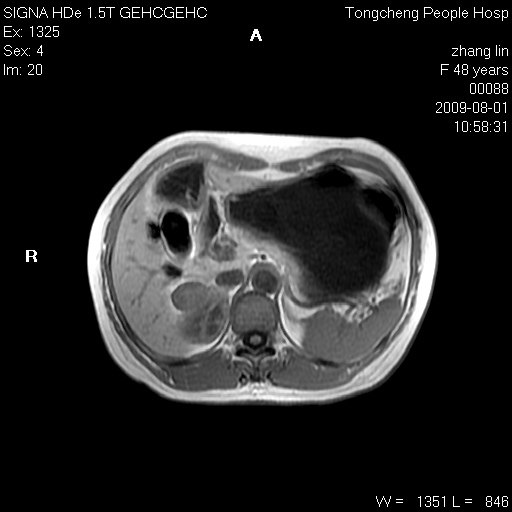

女,48岁。健康体检,彩超发现右肾占位性病变。平素健康。

临床诊断:右肾占位性病变,性质待定(囊肿?肿瘤?)。

上中腹部mr平扫+增强扫描,图像如下:

右肾上极见一类圆形病灶,t1wi呈等信号t2wi呈等高混杂信号,三期增强无强化,边界清---考虑囊肿出血。

同反相位均表现为等信号,病变无强化,考虑含蛋白的囊肿可能,弥散加权相或许有些帮助,

慢性胆囊炎